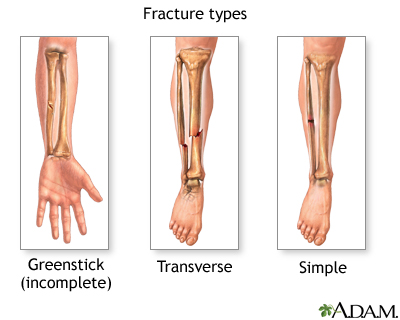

If more pressure is put on a bone than it can stand, it will split or break. A break of any size is called a fracture. If the broken bone punctures the skin, it is called an open fracture (compound fracture).

A stress fracture is a break in the bone that develops because of repeated or prolonged forces against the bone. The repeated stress weakens the bone until it finally breaks.